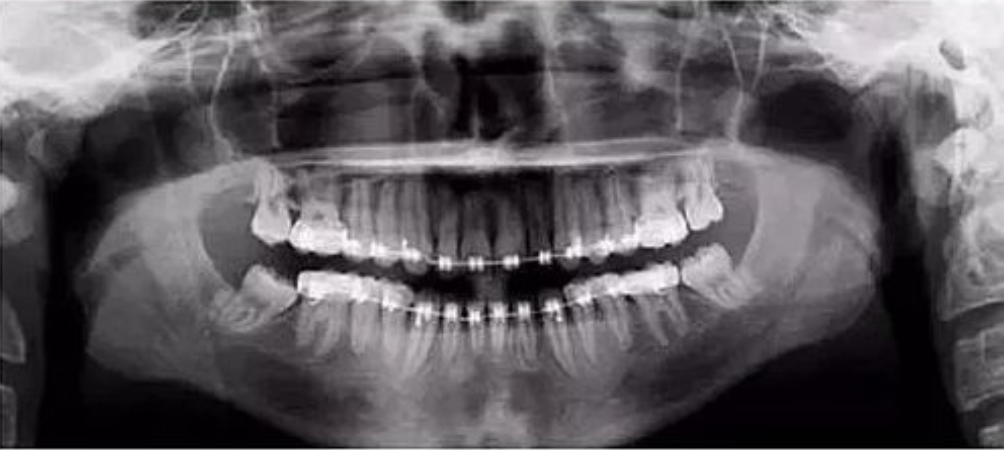

二、影像辐射穿透度不够,前牙显示较大

【失误原因】

定位聚焦激光束或自动对焦(Autofocus)激光束定位过靠前。

【解决方法】

将定位聚焦光束后移至侧切牙根尖位置。